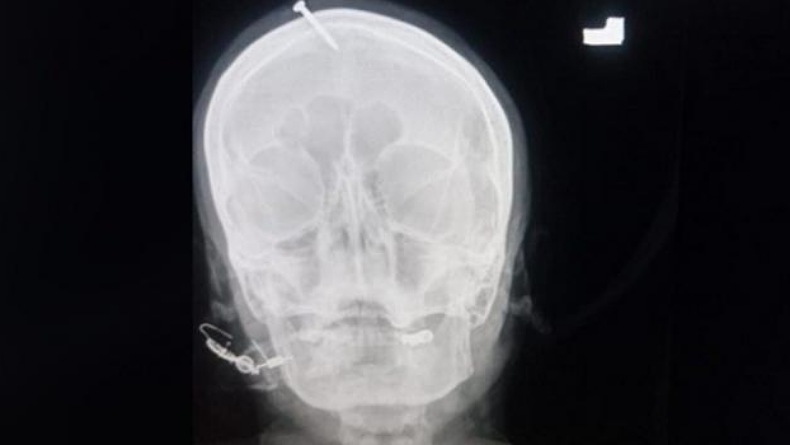

Foto sinar X kepala ibu hamil yang ditancapkan paku oleh dukun di Pakistan. (Foto: Twitter)

Foto sinar X menunjukkan, paku sepanjang 5 cm telah menembus bagian atas dahi perempuan itu, tetapi tidak mengenai otaknya. Khan mengatakan, paku itu tampaknya ditancapkan ke kepala sang ibu dengan palu atau benda berat lainnya.